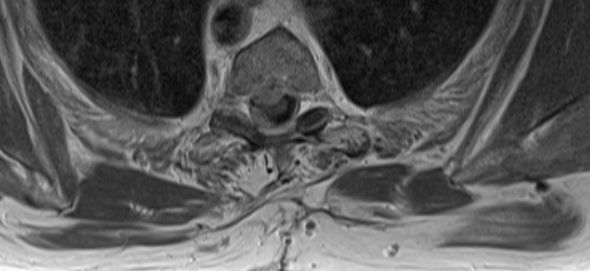

| Rückenmark |

76-jährige Frau mit Rezidiv eines Rückenmarks-Meningeoms. Erstmanifestation vor 17 Jahren. Rezidive von 12, 6 und 3 Jahren jeweils operativ beherrscht. Seit einem Jahr erneut Schmerzen zwischen den Schulterblättern und Druckgefühl im Thoraxbereich. Reduzierter AZ und adipöser EZ. KHK, VHF, Hypertonie, Hypothyreose. Auf Rollator angewiesen. Zunehmende Gangunsicherheit und Kribbeln in den Beinen. Klopfschmerz im Bereich von BWK2-5 stark auslösbar. Die Schmerzen strahlen zeitweise in die Schulterblätter aus. | ![]() | |||||